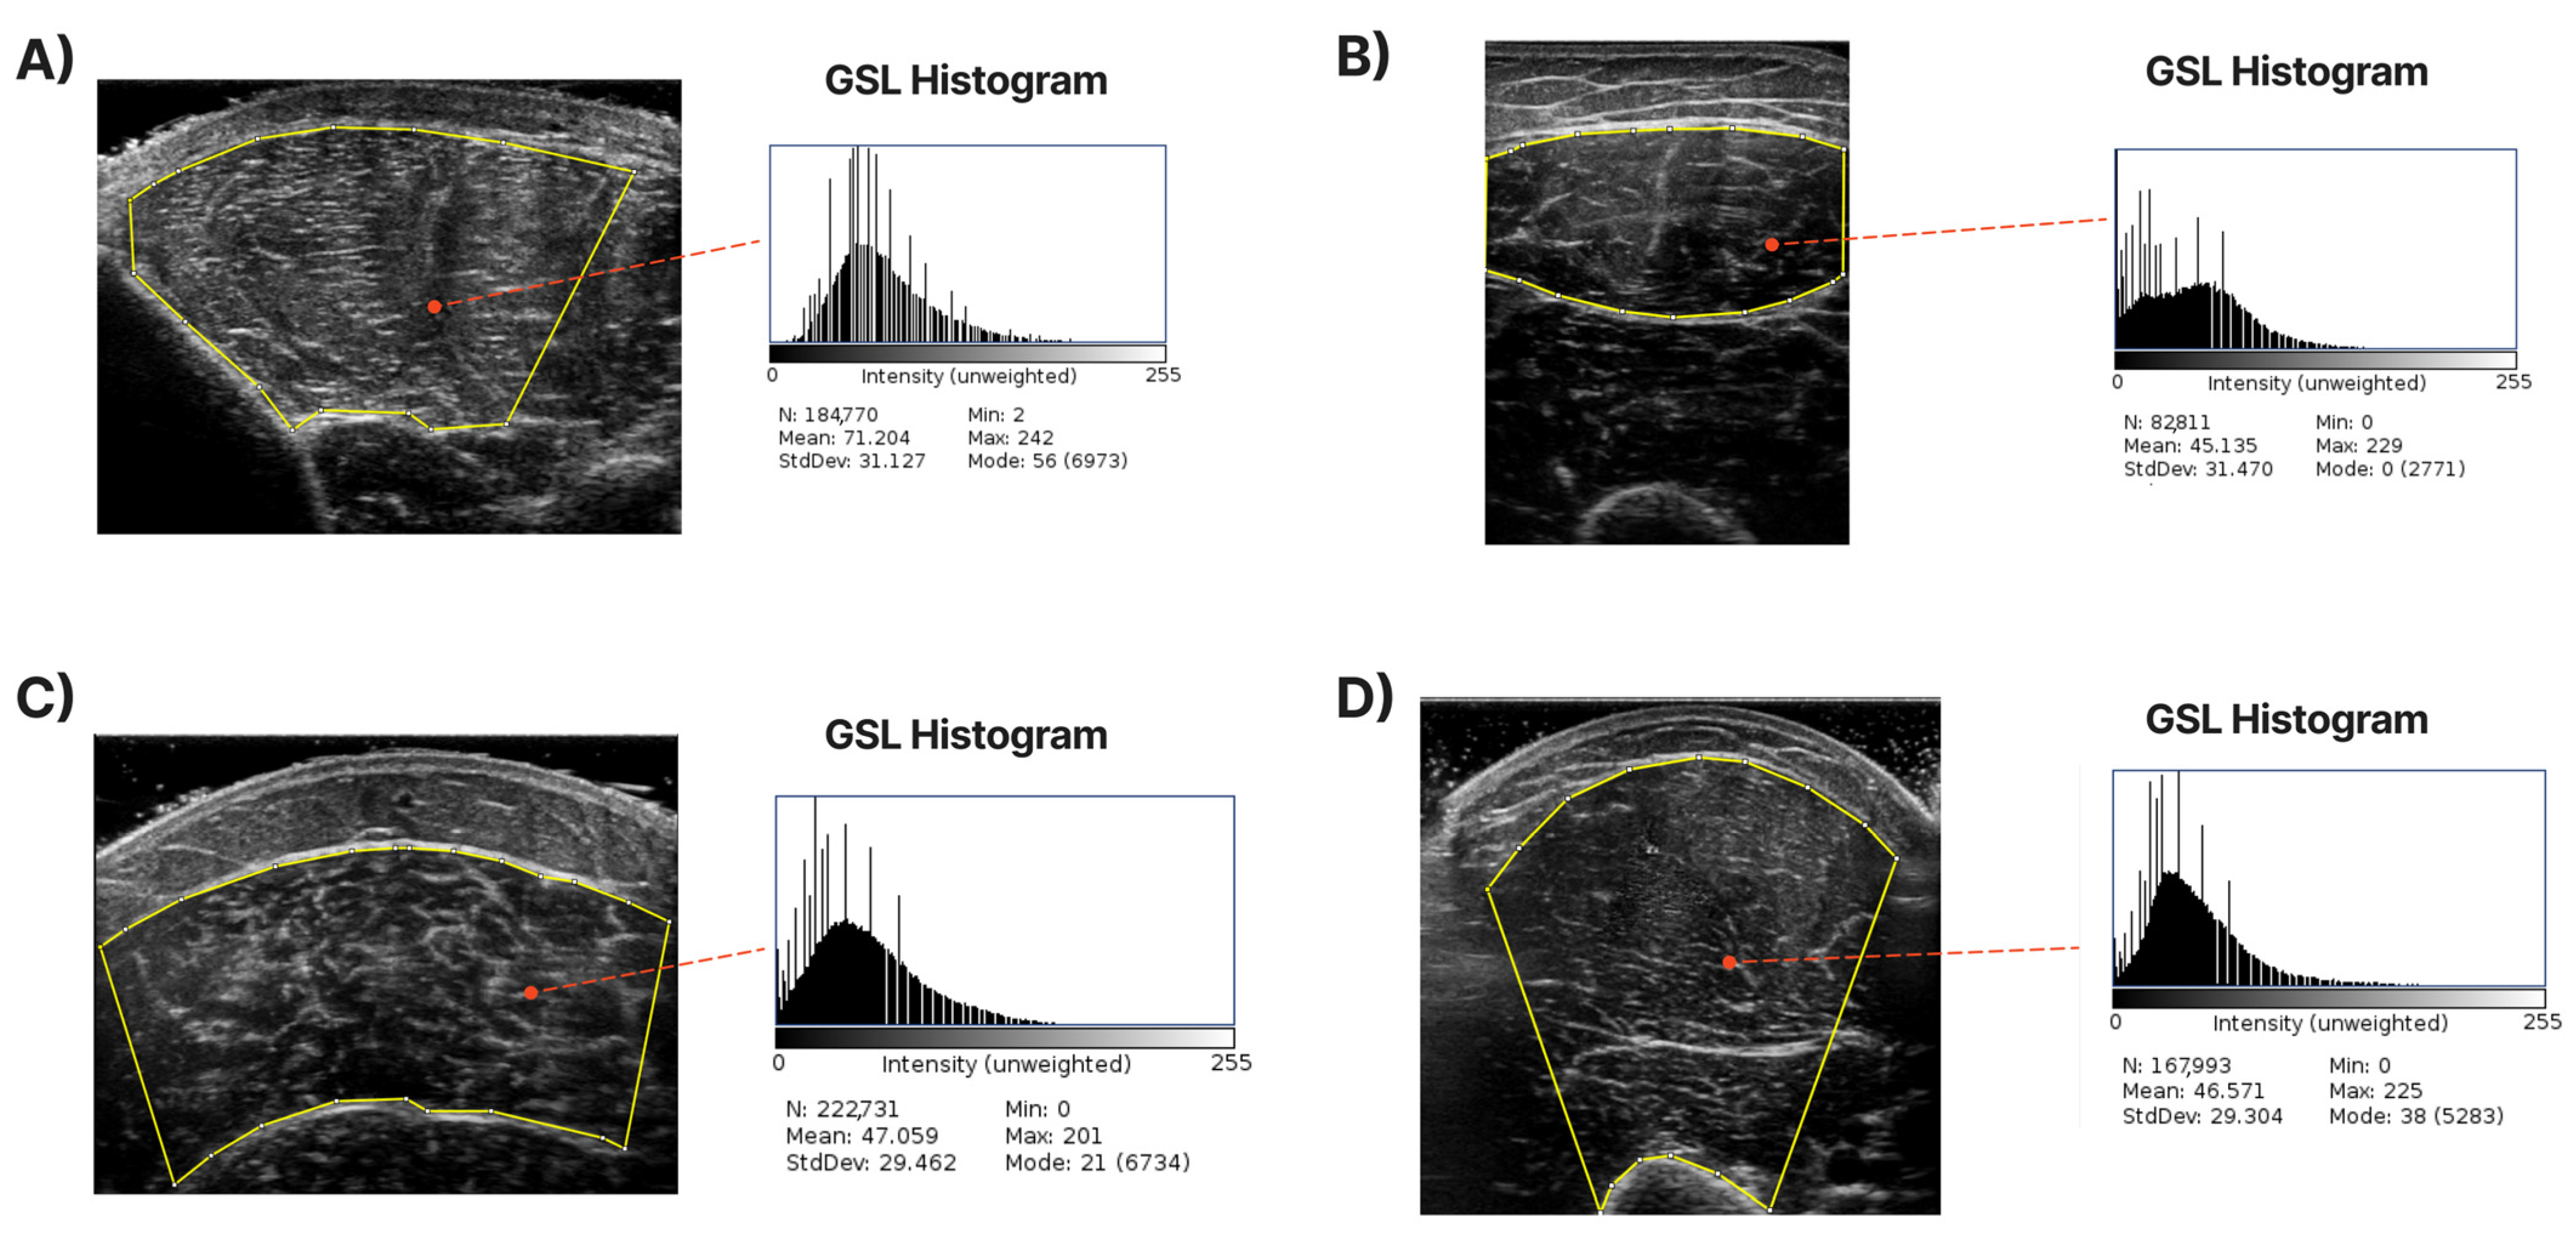

An accurate definition of the CSA in each examined muscle is required to develop a system to extract it automatically. For each muscle, the expert has annotated the maximum visible cross-sectional area (highlighted with the yellow contour in the images of Figure 2) based on his experience but also following the guidelines presented in [4,11]. Specifically, for the T.A., R.F., and B.B., the transverse recording was sufficient to capture the entire muscle in most cases. For the GCM, the whole visible part of the muscle was labelled as the CSA. We tried to omit the areas near edges where artefacts existed since they do not accurately represent the inner muscle and can cause deterioration in the accuracy of muscle echogenicity measurements. In Figure 2, some images, along with their annotated counterparts, are presented. Finally, from the pixels inside the CSA, the mean grayscale level value was calculated to represent the muscle echogenicity as a singular value. This mean () was calculated from the following formula:

where is the grayscale value of the ith pixel, and N is the total number of pixels of the cross-sectional area. Since the CSA was defined in the image plane, the last step was to transform the pixels into physical units (mm2) by multiplying accordingly by the pixel size retrieved from the DICOM metadata provided by the ultrasound machine.

Figure 2.

Sample of ultrasound images with their corresponding annotation. The CSA area contours are depicted with yellow lines. The grayscale level (GSL) histogram and its mean value are extracted inside the CSA. (A) shows the measurements of T.A., (B) shows the measurements of R.F., (C) shows the measurements of the GCM, and (D) demonstrates B.B.